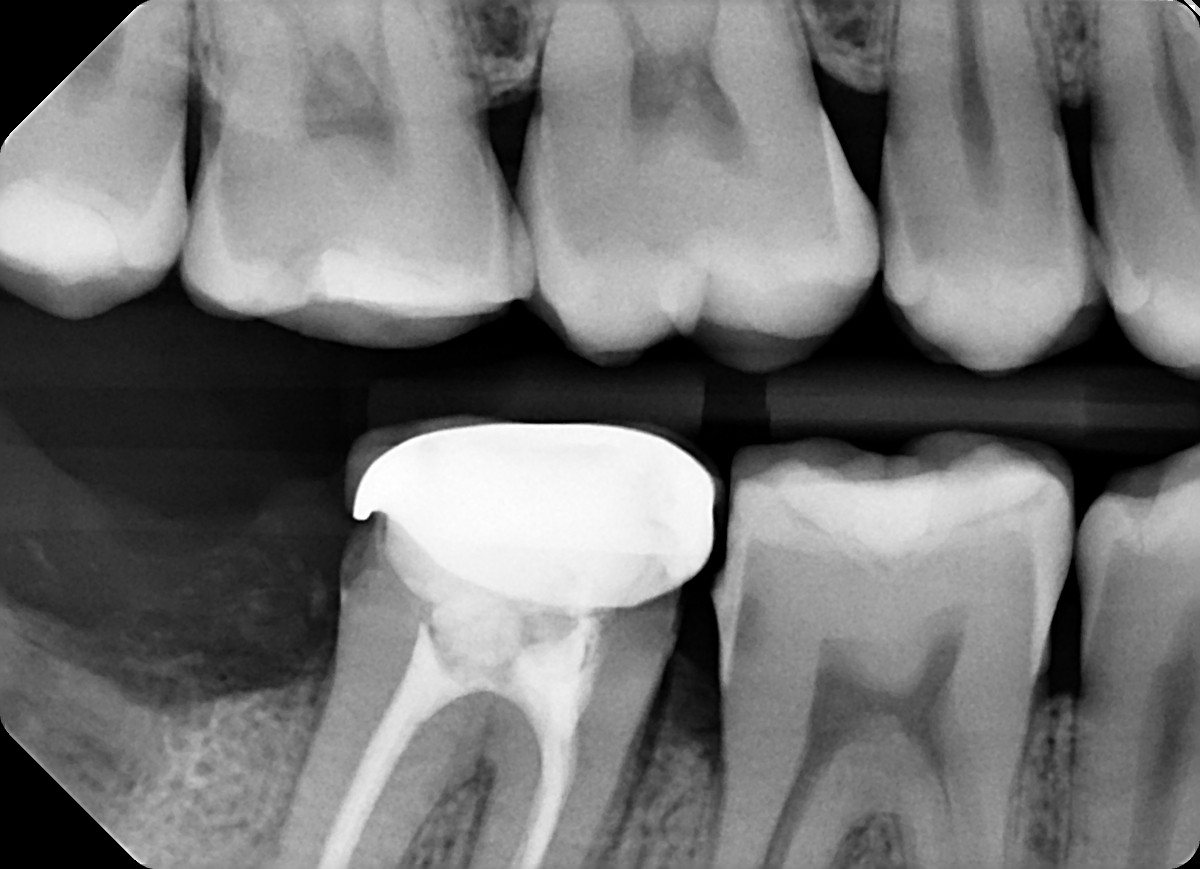

8. What option can explain the crown of the tooth #4.6?